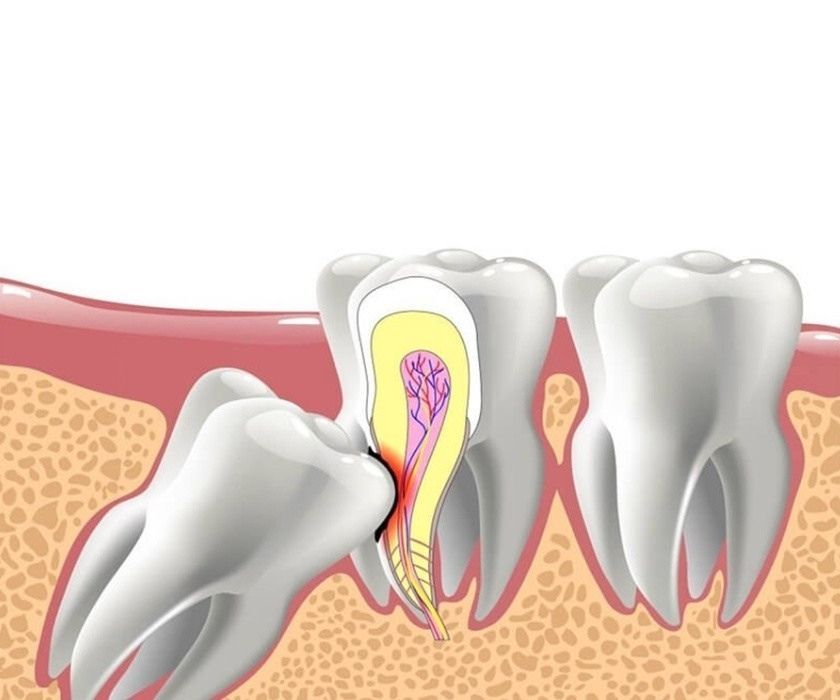

Một chiếc răng khôn được coi là mọc lệch khi nó không mọc thẳng đứng mà có xu hướng mọc nghiêng về phía răng số 7 (răng hàm lớn thứ hai), mọc lệch ra má, hoặc thậm chí là mọc ngầm hoàn toàn dưới lợi và xương hàm. Tình trạng này có thể xảy ra ở cả hàm trên và hàm dưới, nhưng phổ biến và gây đau đớn hơn ở hàm dưới.

• Sâu răng và viêm nha chu: Răng khôn mọc lệch tạo ra những khe hở hẹp với răng số 7, là nơi thức ăn và vi khuẩn dễ dàng mắc kẹt. Vị trí này rất khó vệ sinh bằng bàn chải thông thường, dẫn đến sâu răng ở cả răng khôn và răng số 7. Nếu không điều trị, vi khuẩn sẽ phát triển, gây viêm nha chu, viêm nướu và làm tổn thương các mô xung quanh.